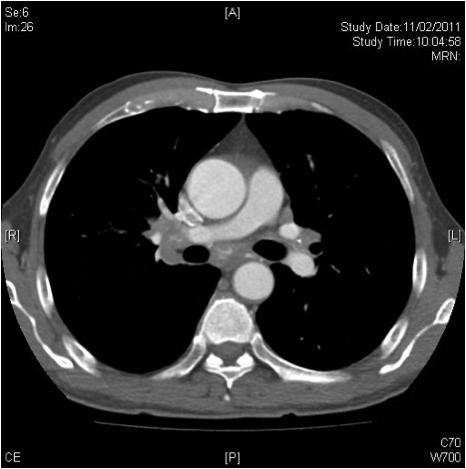

Computer tomography (CT) of chest was done (Fig 2A, 2B). It showed widespread tree-in-bud opacities, septal thickening, mild bronchiectasis and mildly dilated bronchi with wall thickening. The bone window of CT scan showed multiple enlarged mediastinal and hilar lymph nodes. Bronchoscopy with transbronchial biopsy at right lung found bronchiocentric foci of polymorphous inflammatory infiltrate with lymphocytes, plasma cells, eosinophils and neutrophils. There was no granuloma. It suggested interstitial inflammation with eosinophilia.